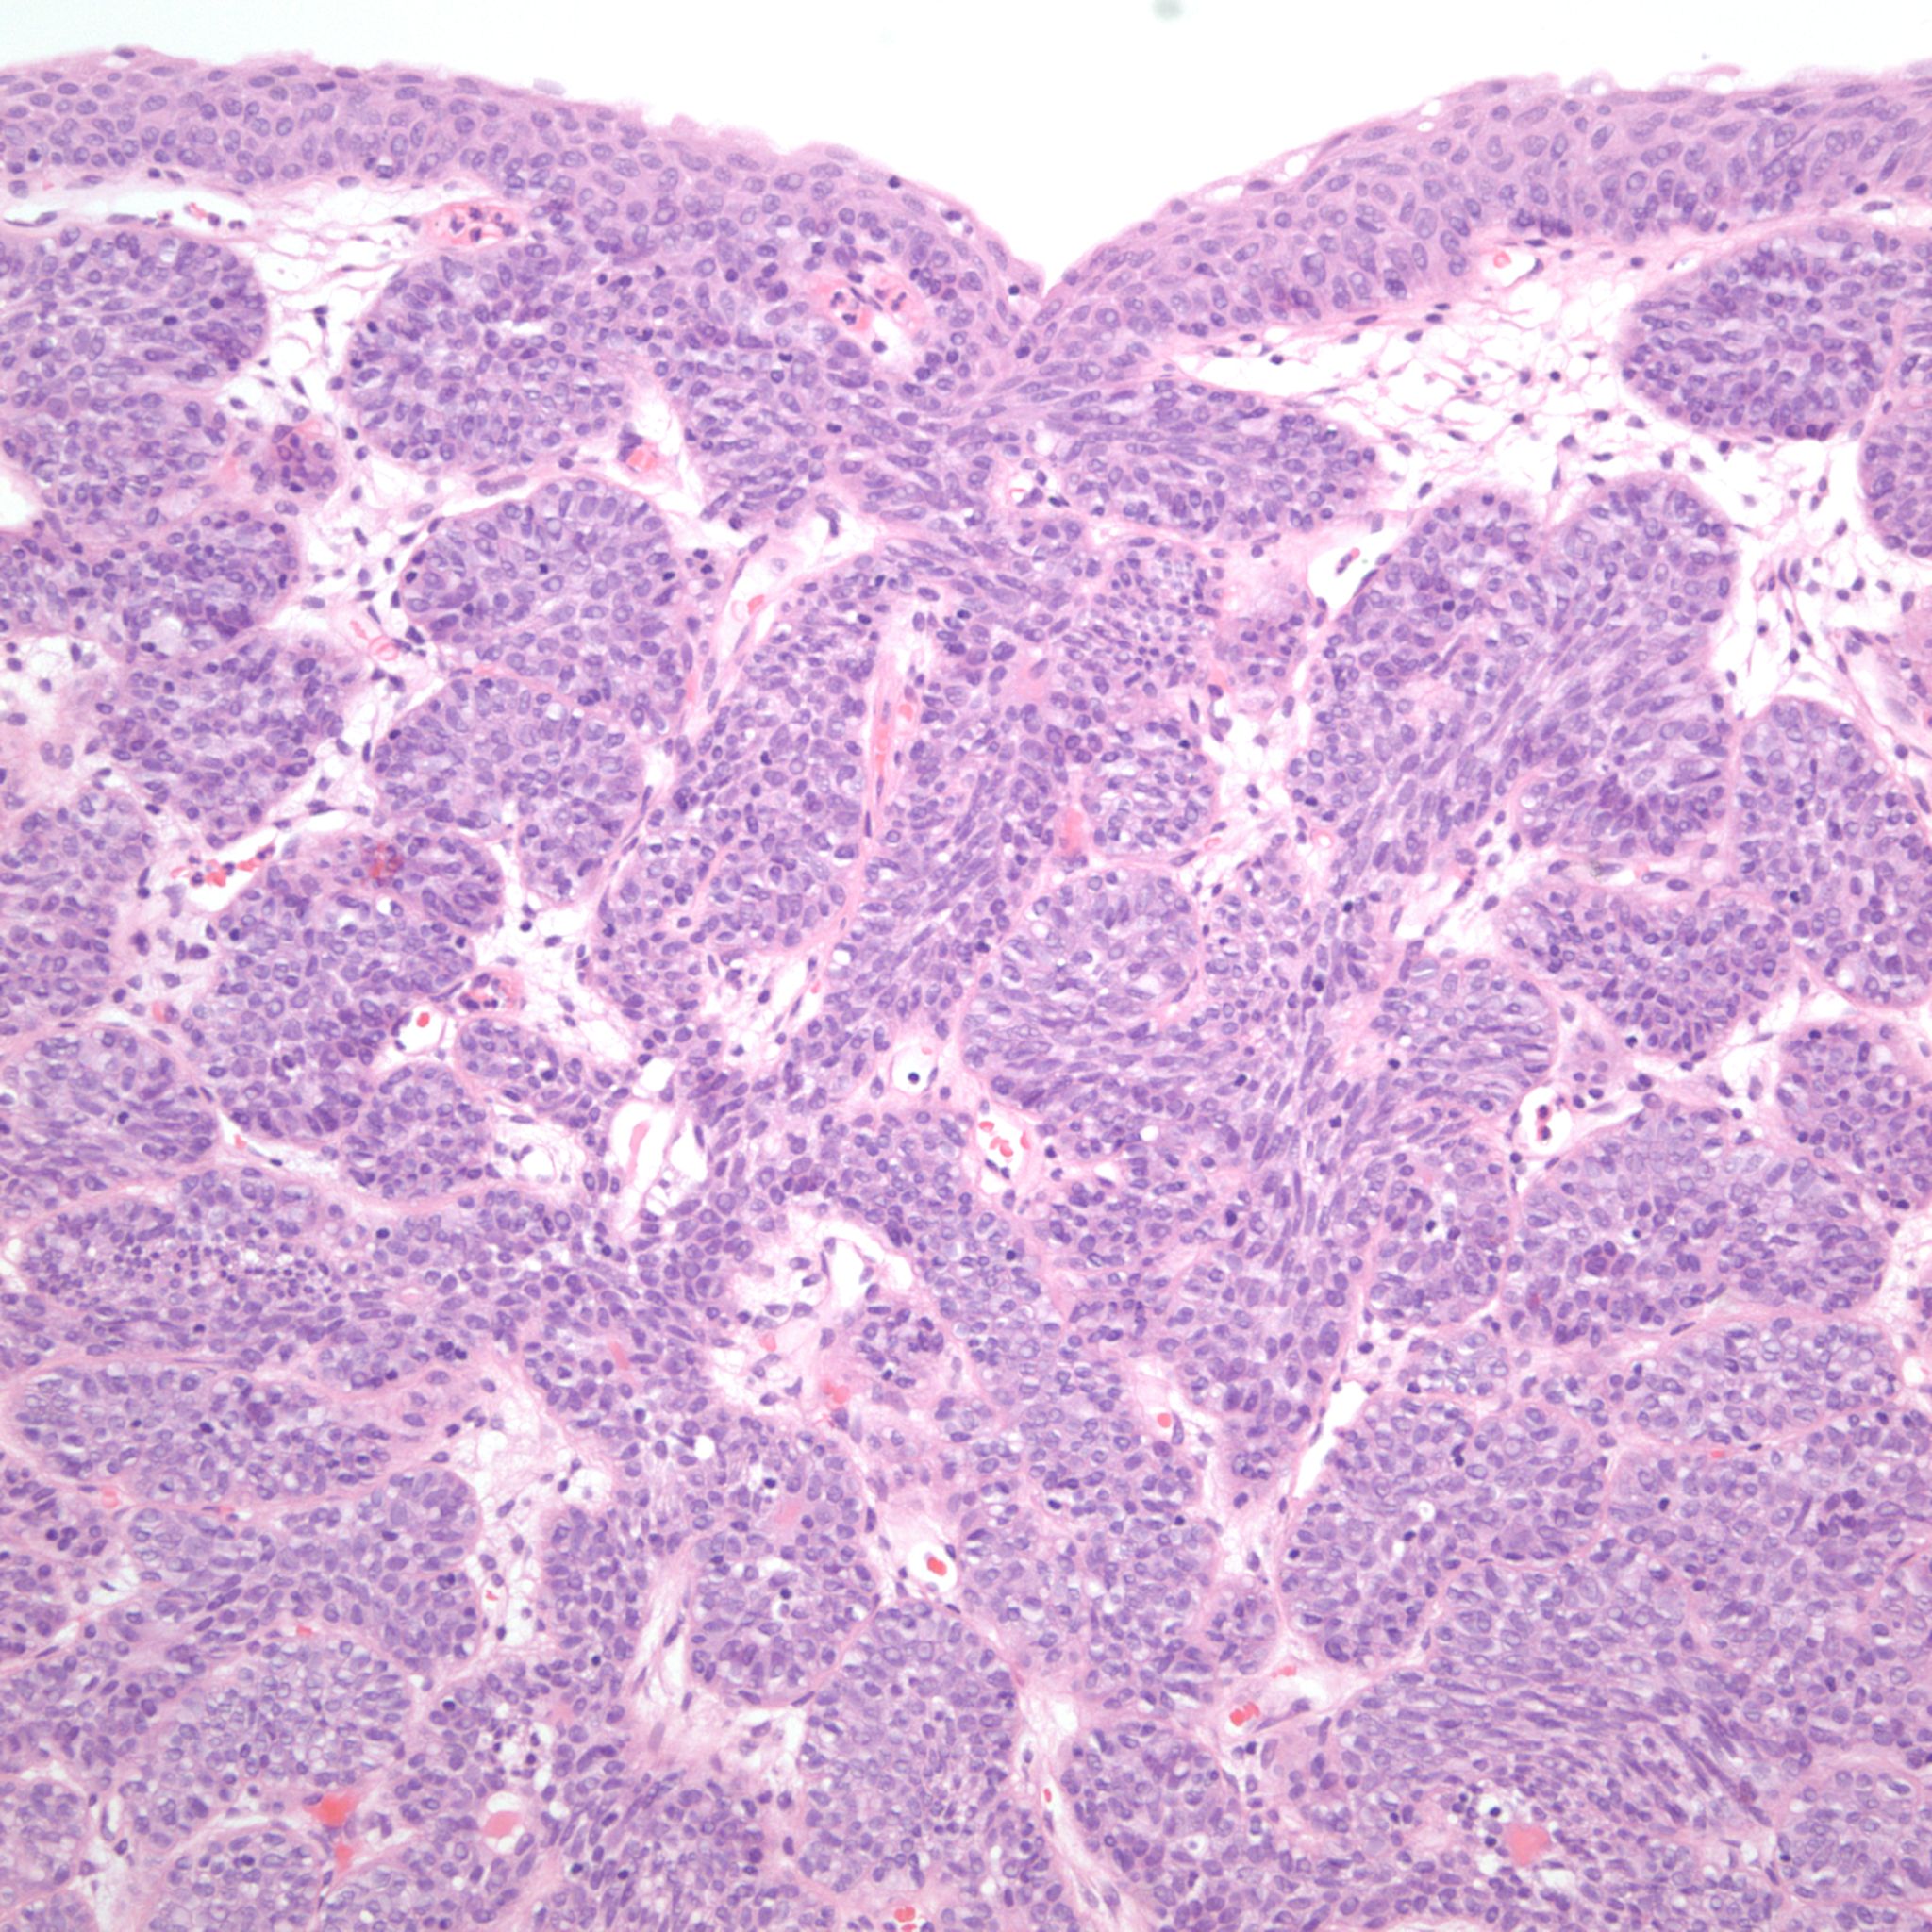

Bladder Papillary Lesions

Case ID: 309

Papilloma

PUNLMP

Low-grade papillary urothelial carcinoma (LG-PUC)

High-grade papillary urothelial carcinoma (HG-PUC)